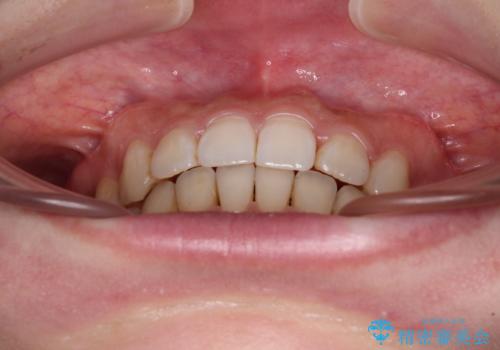

- 前歯のデコボコと深い咬み込みを気にして来院された患者様です。

インビザラインを用いて、前歯の叢生を解消するとともに、深い咬み合わせ(ディープバイト)を改善していくこととしました。

奥歯を後方に直立させることで深い咬み合わせを改善を図り、隠れていた下顎前歯が見えるほどになりました。